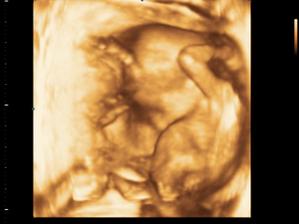

Baby # 3